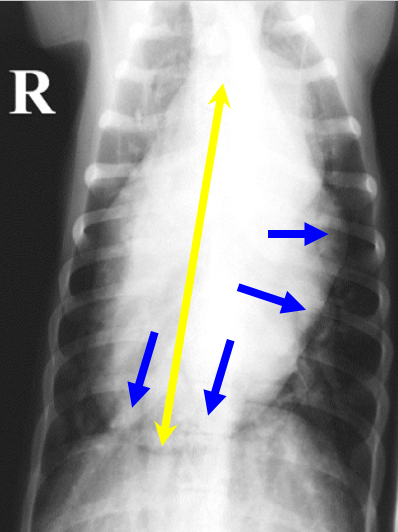

What can be seen here?

Right-sided heart enlargement in dogs

Right ventricle will extend cranially, will increase width of cardiac silhouette and increase sternal contact

Not as much increase in height